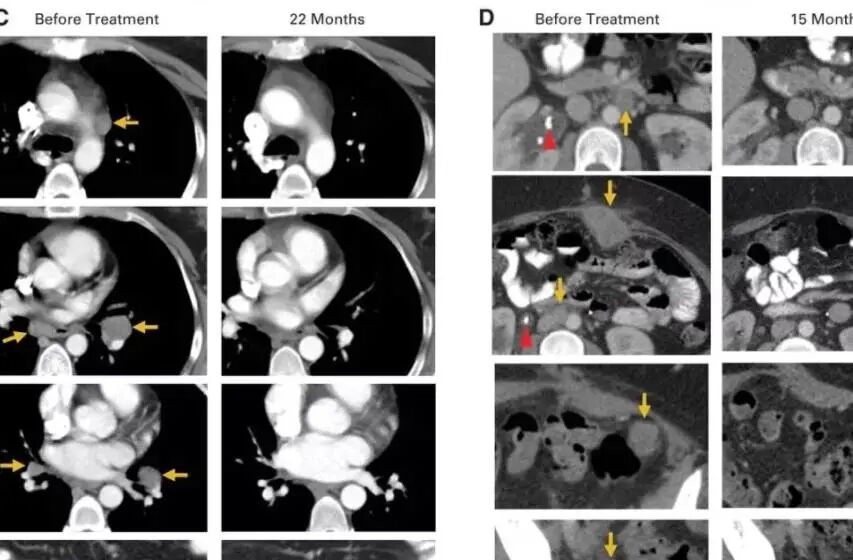

2018年,美国研究人员宣布,成功利用免疫疗法彻底治愈一名宫颈癌患者,且已5年未复发,这也是世界范围内首例使用免疫疗法治愈宫颈癌的案例。

名被治愈的宫颈癌患者Sue Scott,当时36岁,经过多轮化疗、放疗和手术治疗,依然没有阻止癌细胞扩散,迅速侵入她的肝脏和结肠,并挤压她的输尿管。

随后,Scott参加了一项由美国国家卫生研究院临床中心(世界上从事生命科学研究最重要的研究机构之一)组织的免疫治疗治疗试验,在该实验中,医生通过手术切除她的部分肿瘤,研究人员将免疫细胞注入患者体内,形成一支免疫大军,靶向攻击癌细胞,最终成功将癌细胞“干掉”。

一个月后,她的复查结果显示:肿瘤明显缩小了。特别是腹部凸起的肿瘤已经不见了!

治疗两个月后,Scott的复查结果再次震惊了所有人,包括她自己,影像学检查显示,她的体内已经没有任何癌症的迹象。Scott开心地笑了,又哭了,她觉得这是几年来自己第一次畅快的呼吸。

2015年5月,Hinrichs博士第一次将他参与的这项临床试验的结果在肿瘤会议上公布,9名患者中的2名-Scott和AriccaWallace女士的转移性肿瘤全部消失了,完全缓解时间已超过两年。

2018年3月,她庆祝了癌症康复5周年,医生告诉她,她的癌症已经完全治愈。